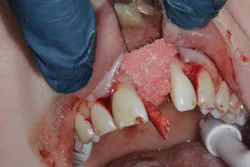

Gum recession around dental implants due to craniofacial development is a significant concern in implant dentistry, with the potential to undermine both the esthetic and functional success of dental implant procedures. When the gum tissue surrounding the implant site begins to recede, it can expose the underlying adjacent tooth root or the surface of the dental implant itself (figure 5). This not only affects the natural appearance of the artificial tooth but also increases the risk of dental implant failure and other complications.

For patients who already exhibit signs of gum recession around their dental implants, advanced treatments such as bone grafting may be necessary to restore the supporting bone and stabilize the implant (figure 6). Addressing the underlying causes—such as correcting poor oral hygiene habits, managing teeth grinding, and treating existing gum disease—is critical to prevent recurrence and ensure the longevity of the implant.